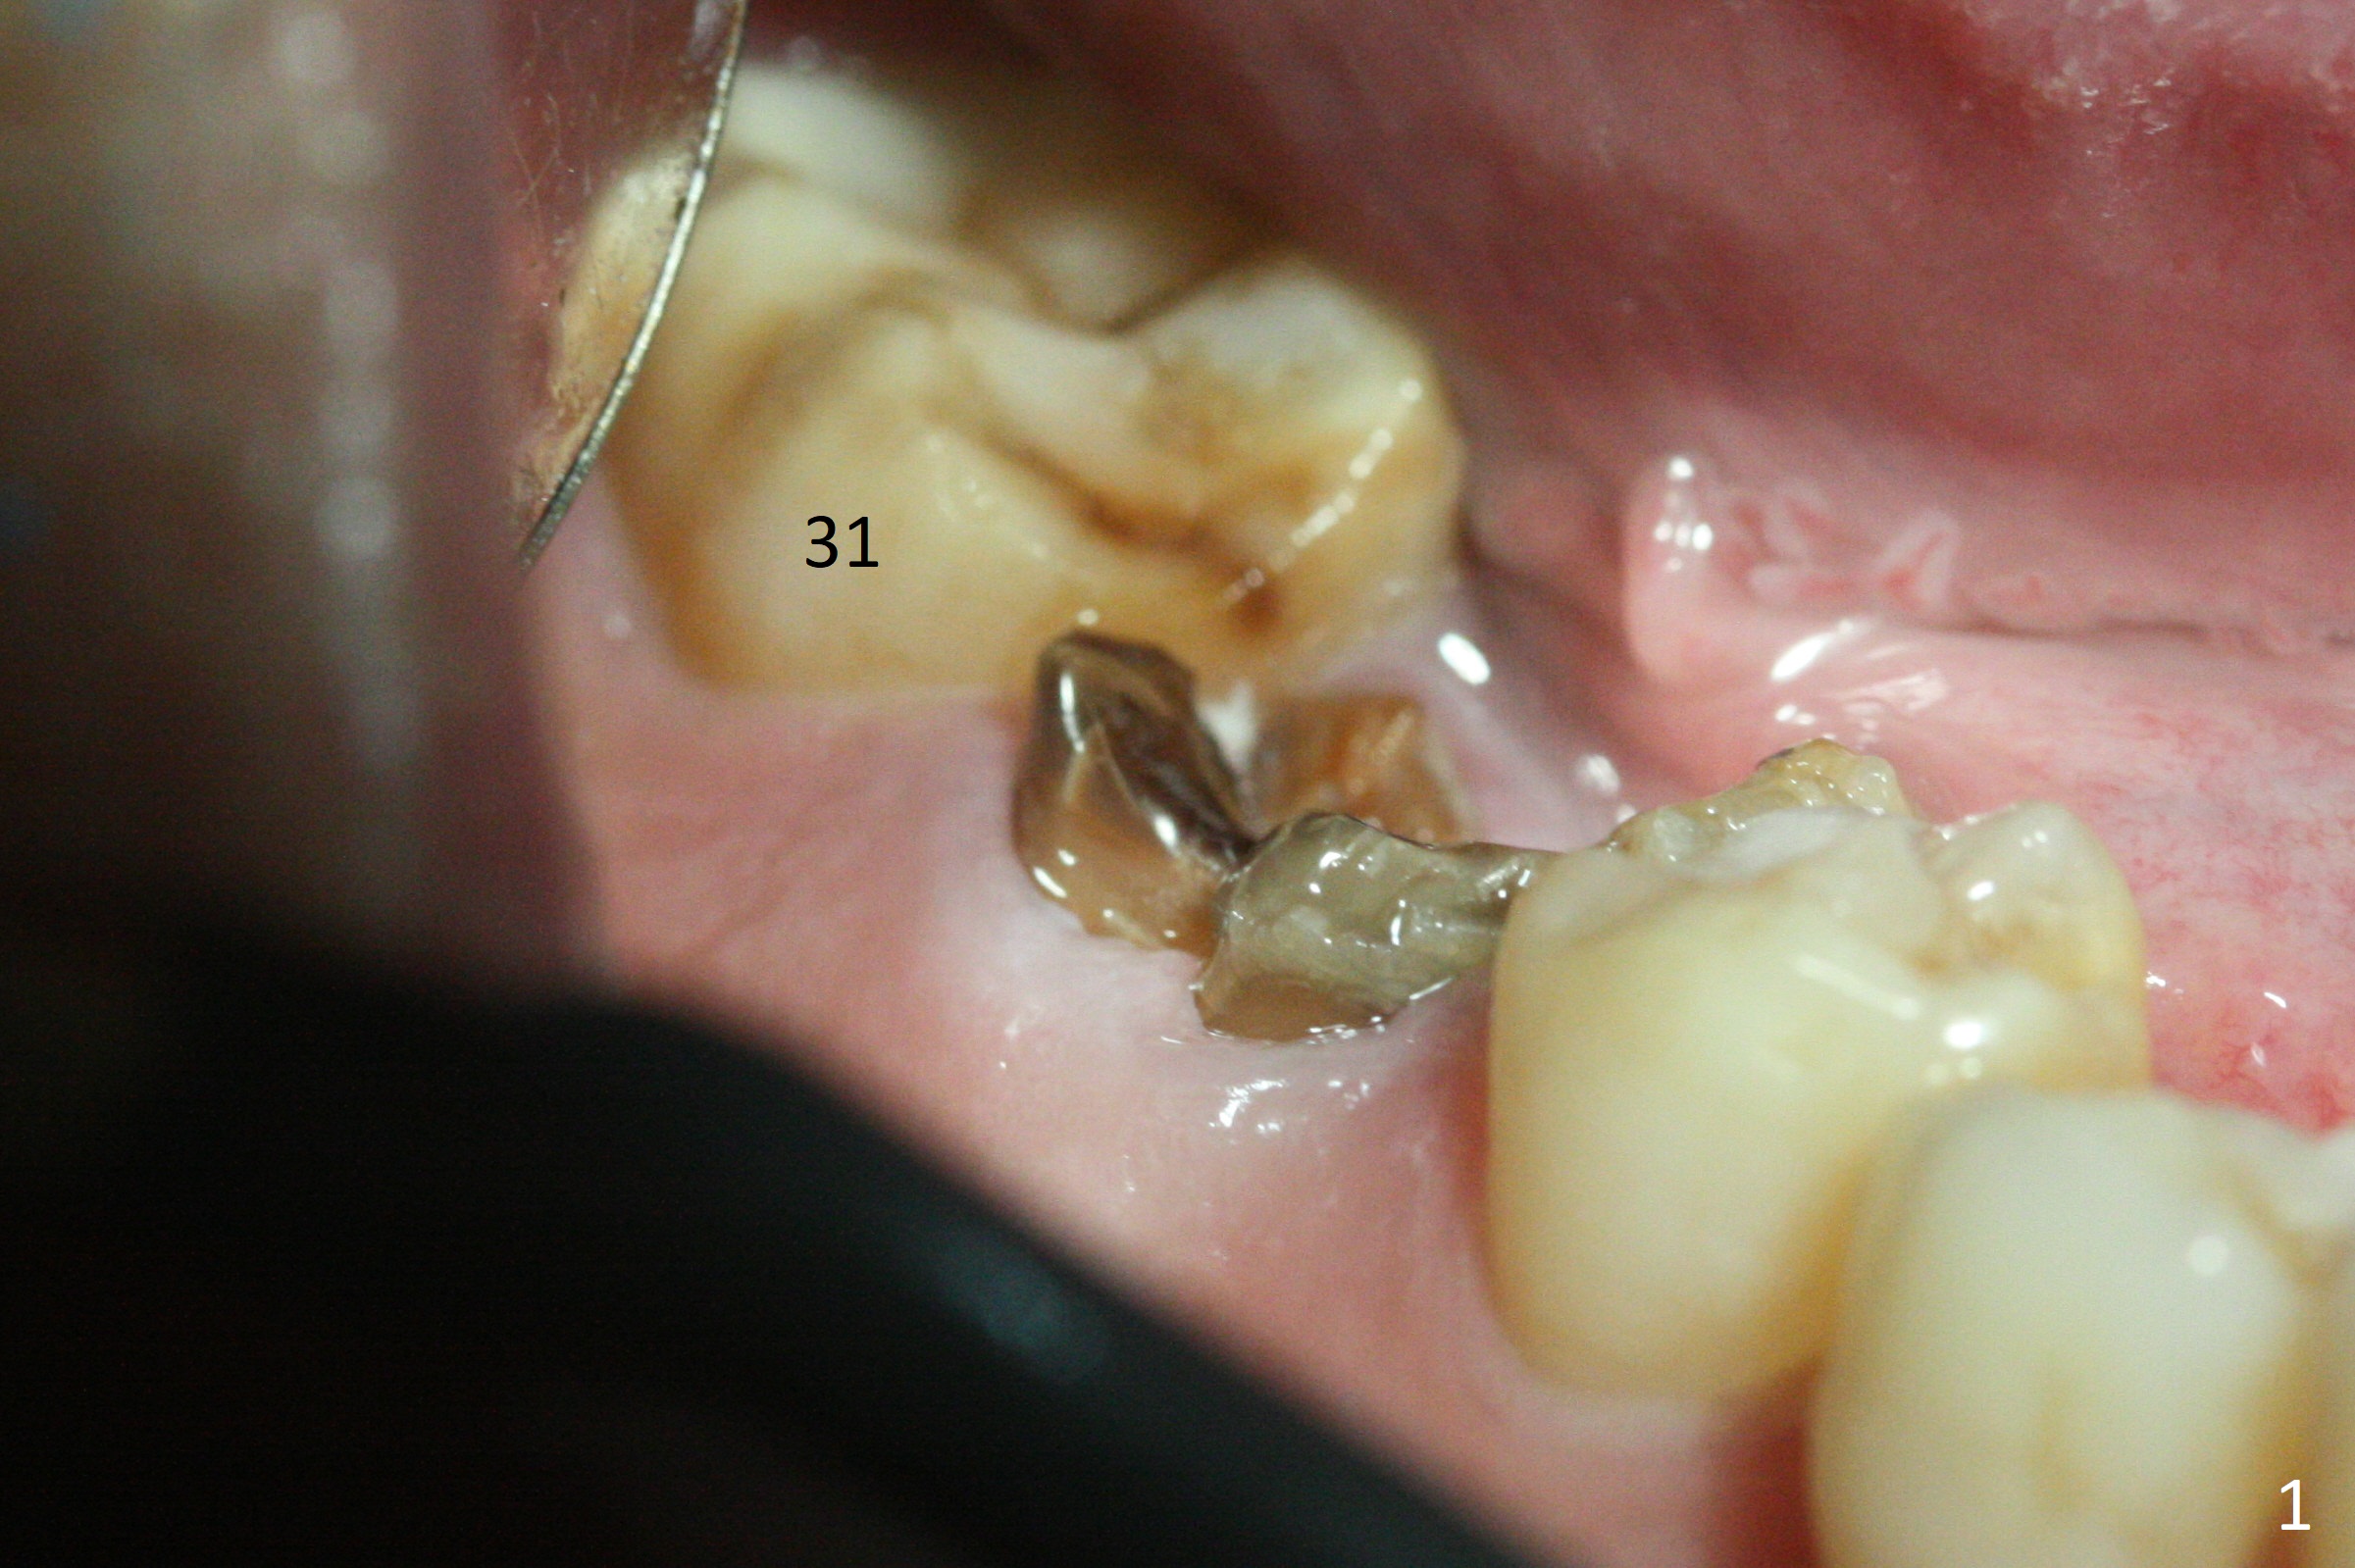

After removal of the residual roots at #30 (Fig.1), a thin septum (Fig.2 *) is removed with Rongeur (Fig.3). Following use of 4.8 mm Magic Drill, a 5x9 mm dummy implant is placed (Fig.4). To reduce socket gap (*), a 6 mm IBS implant is inserted with >50 Ncm (Fig.5). What is unexpected is heavy reduction in the height of a 6.5x4(3) mm abutment (A) because of the short crown height of the lower posterior teeth (Fig.1) and supraeruption of the tooth #3. The immediate provisional is unstable postop. The remade one dislodges soon, so does the abutment (Fig.6, 3 months postop). It appears that bone pattern in the distal socket changes.